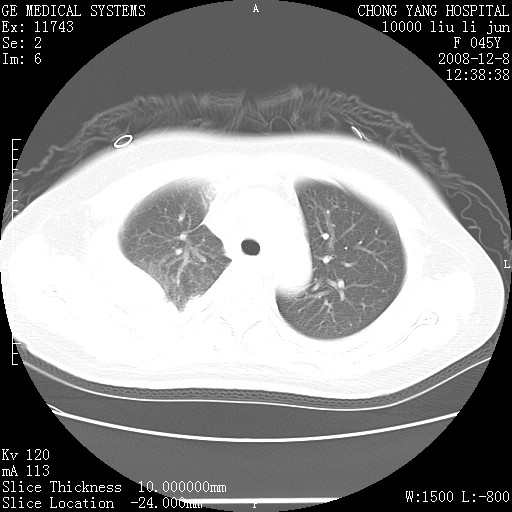

标题: CT20268:肺泡癌?间质性肺炎? [打印本页]

标题: CT20268:肺泡癌?间质性肺炎?

女,62岁,近二年经常咳嗽,近二个月,消瘦、乏力。

前面一张胸片是今天照的,后面一张胸片是去年9月份的。